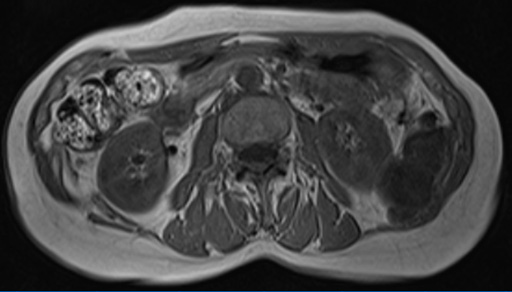

図1 腹部造影CT

図1 腹部造影CT

(右腎上極レベル) 図2 腹部造影CT